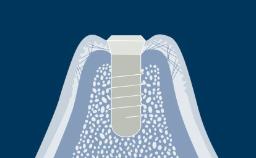

O clínico que pratica implantodontia é confrontado com diferentes situações clínicas, que variam de um único dente ausente, a um espaço edêntulo com vários dentes ausentes até completar rebordos totalmente edêntulos. Uma vez estabelecido um plano de tratamento completo, diferentes desenhos de configurações podem ser possíveis para próteses implantossuportadas. Cada desenho da prótese tem suas vantagens e desvantagens. O desenho da prótese deve basear-se na condição clínica para garantir que o número apropriado de implantes seja instalado nas posições protéticas corretas usando implantes com dimensões apropriadas.